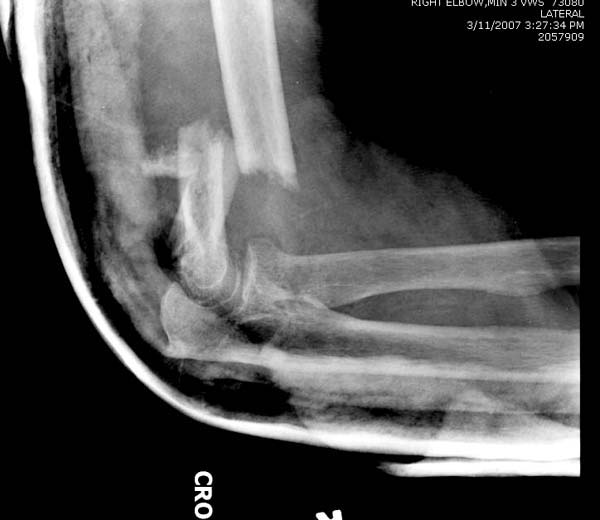

Из представленнего материала видно, что между снимками нет разницы. Отсутствует репозиция не только медиального, а также латерального мыщелка. На боковом снимке мыщелок расположен спереди, а прямом головка луча упирается в край мыщелка, что означает ротацию. Отсутствует компрессия между мыщелками, а один шуруп не смог удержать медиальную сторону, которая при первом же движении рассыпалось.

Ошибка в фиксации привела к дополнительным проблемам, теперь, кроме плеча, надо заниматься с локтевым отростком и невритом. Доступ обычно из двух сторон мышцы трицепса, но некоторым внутрисуставным переломам визуализацию можно создать за счет остеотомии локтевого отростка и как дружно заявили, что фиксацию заканчивает только по Веберу.